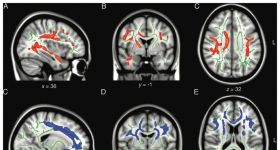

來(lái)自麻省總醫(yī)院的Matthew N. DeSalvo等人認(rèn)為,術(shù)前fMRI腦網(wǎng)絡(luò)的整合狀況可以預(yù)測(cè)顳葉癲癇患者的術(shù)后結(jié)果。基...